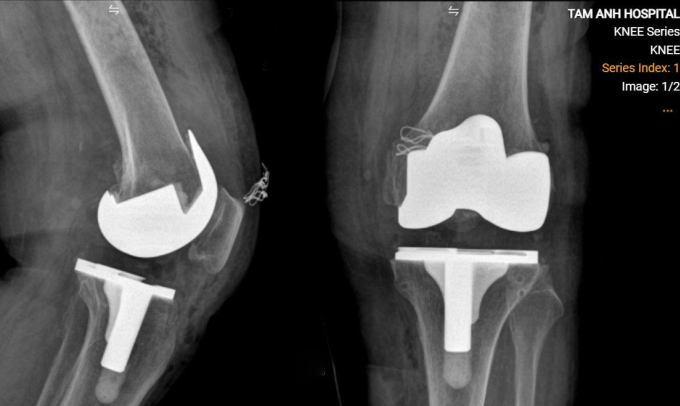

Khớp gối nhân tạo của bà Tịch. Ảnh: Bệnh viện Đa khoa Tâm Anh

Bác sĩ chụp cắt lớp vi tính CT, tái tạo khớp gối lên môi trường 3D, giúp đo đạc chính xác các thông số để chọn loại khớp phù hợp, xác định vị trí và hướng đặt khớp, cân bằng sức căng dây chằng cho bà. Khi mổ, bà Tịch được gây tê tủy sống, kết hợp thuốc an thần nhẹ để ngủ thoải mái, tránh biến chứng của gây mê toàn thân. Bác sĩ Nghĩa rạch bộc lộ khớp gối, cắt xương và đặt khớp nhân tạo cho người bệnh, hơn một tiếng ca mổ hoàn thành.